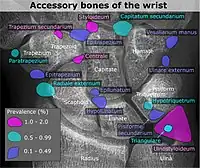

Poignet et main

| Os accessoire | Prévalence à droite (R) et à gauche (L) [3] |

|---|---|

| Os ulnostyloideum | 1,5 % R, 2,4 % L |

| Os central du carpe | 1,3 % R, 2,1 % L |

| Os trapèze secondaire | 0,5 % R, 2,1 % L |

| Os styloïdeum | 1,2 % R, 1,2 % L |

| Os radiale externum | 1 % R, 0,9 % L |

| Os triangulare | 1 % R, 0,9 % L |

| Os paratrapezium | 0,3 % R, 0,9 % L |

| Os capitatum secondaire | 0,8 % R, 0,3 % L |

| Os hypotriquetrum | 0,5% R |

| Os hypolunatum | 0,3%L |

| Os épilunatum | 0,3% R, 0,3% L |

| Os ulnare externum | 0,3%L |

| Os pisiforme secondaire | 0,3% R |

| Os epitrapezium | 0,3%L |

| Os vesalianum manus | 0,3%L |